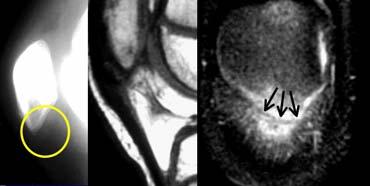

TRÁI: Dập xương lồi cầu ngoài (vòng tròn vàng). MCL bình thường (mũi tên xanh lá) nhưng không thấy dây chằng xương bánh chè – lồi cầu đùi phía trước. PHẢI: Dây chằng xương bánh chè – lồi cầu đùi phía trong bị đứt khỏi điểm bám tại xương đùi.

Ca bệnh bên trái là một nữ cầu thủ bóng đá bị xoắn vặn khớp gối.

Bốn hình ảnh MRI từ dưới lên trên thể hiện đầy đủ các đặc điểm hình ảnh của trật khớp xương bánh chè kèm đứt dây chằng xương bánh chè – lồi cầu đùi phía trong.

Xương bánh chè bị trật và mặt khớp phía trong đã va đập vào lồi cầu ngoài xương đùi.

Xương bánh chè đã tự trở về vị trí bình thường.

Tổn thương dập xương có thể kèm theo biến chứng gãy sụn khớp.